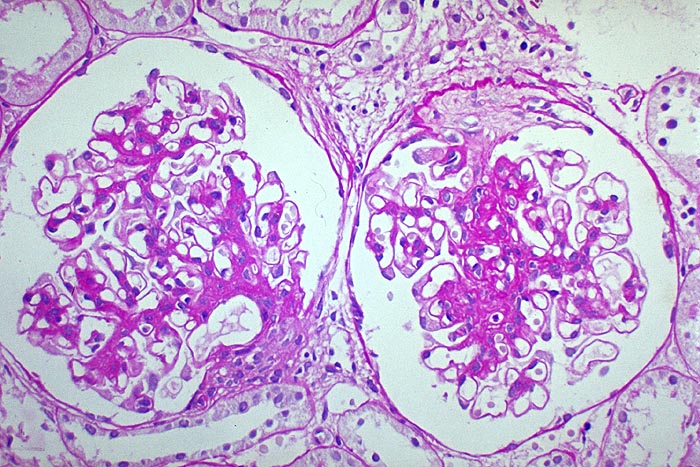

mesangioproliferative Glomerulonephritis bei IgA-Nephritis

In einem der Glomeruli ist eine deutliche Mesangiumverbreiterung erkennbar ohne auffallende Zellvermerhung. Im anderen Glomerulus ist ein Schlingensegment besonders stark betoffen. Darüber liegt ein sklerosierter Halbmond.

Bei der IgA Nephritis sind alle morphologischen Formen der Glomerulonephritis möglich ausser die epimembranöse Glomerulonephritis.

glomeruläre Minimalveränderungen bei 15%

Mesangioproliferative Glomerulonephritis bei 25%

segmental fokal proliferative Glomerulonephritis bei 55%

häufig segmentale extrakapilläre Halbmonde.